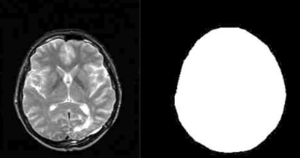

Background/Purpose: This study presents a novel automatic approach for the identification of anatomical brain structures in magnetic resonance images (MRI). The method combines a fast multiscale multi-channel three dimensional (3D) segmentation algorithm providing a rich feature vocab ulary together with a support vector machine (SVM) based classifier. The segmentation produces a full hierarchy of segments, expressed by an irregular pyramid with only linear time complexity. The pyramid provides a rich, adaptive representation of the image, enabling detection of various anatomical structures at different scales. A key aspect of the approach is the thorough set of multiscale measures employed throughout the segmentation process which are also provided at its end for clinical analysis. These features include in particular the prior probability knowl- edge of anatomic structures due to the use of an MRI probabilistic atlas. An SVM classifier is trained based on this set of features to identify the brain structures. We validated the approach using a gold standard real brain MRI data set. Comparison of the results with existing algorithms displays the promise of our approach.